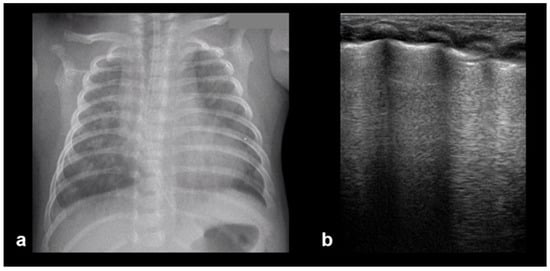

Normal to mild RDS: by chest X-ray (a); by LUS (b).

Figure 14.